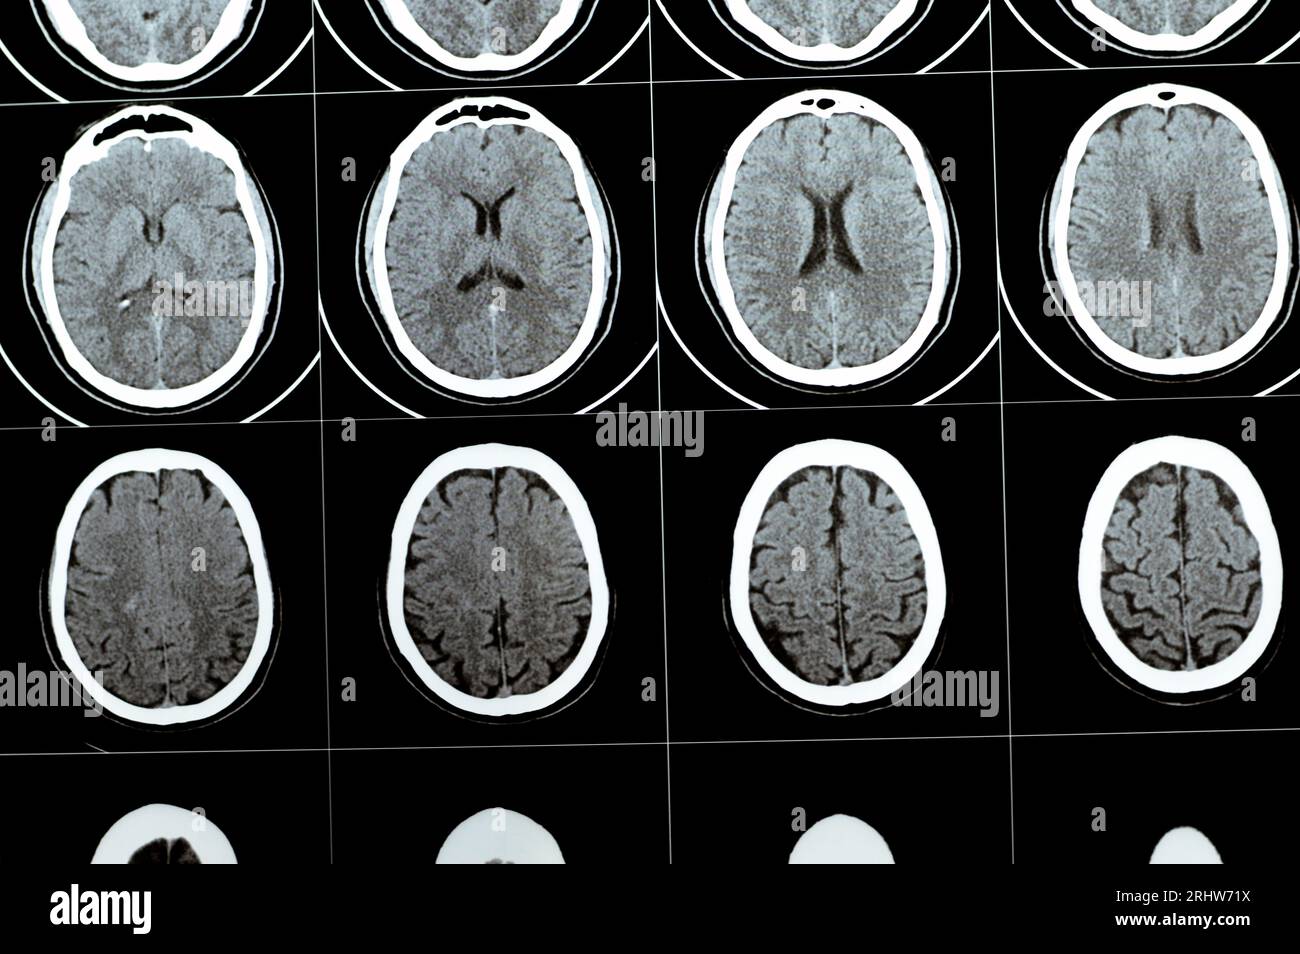

Brain CT Scan stock image. Image of ishemia, monitor 23851097 What Is The Purpose Of A Brain Ct Scan computed tomography (ct) scans of the head are an important diagnostic tool in modern medicine,. a cranial ct scan is a diagnostic tool used to create detailed pictures of features inside your head, such as your skull, brain, paranasal. ct scans may be used to diagnose headaches when neuroimaging is indicated and mri is not available, or. What Is The Purpose Of A Brain Ct Scan.

CT scan of brain show normal human 's brain ( CAT scan Stock Photo What Is The Purpose Of A Brain Ct Scan a ct (computed tomography) scan is an imaging test that helps healthcare providers detect diseases and injuries. ct scans may be used to diagnose headaches when neuroimaging is indicated and mri is not available, or in emergency settings when hemorrhage, stroke, or. computed tomography (ct) scans of the head are an important diagnostic tool in modern medicine,.. What Is The Purpose Of A Brain Ct Scan.

Ct scan brain stock image. Image of radiology, computed 16241927 What Is The Purpose Of A Brain Ct Scan a cranial ct scan is a diagnostic tool used to create detailed pictures of features inside your head, such as your skull, brain, paranasal. A ct scan of the brain may be used to check the brain for the following: ct scans may be used to diagnose headaches when neuroimaging is indicated and mri is not available, or. What Is The Purpose Of A Brain Ct Scan.